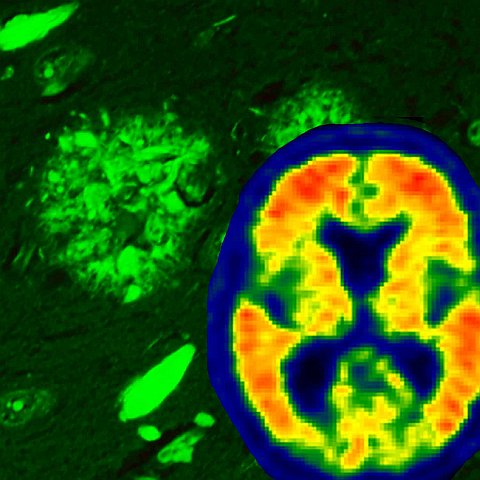

Cosa accade nel cervello che invecchia

Il deterioramento del cervello si insinua sulla maggior parte di noi. Il primo indizio p...

Svelata una teoria rivoluzionaria sull'origine dell'Alzheimer

Nonostante colpisca milioni di persone in tutto il mondo, il morbo di Alzheimer (MA) man...

L'Alzheimer è composto da quattro sottotipi distinti

Il morbo di Alzheimer (MA) è caratterizzato dall'accumulo anomale e dalla diffusione del...